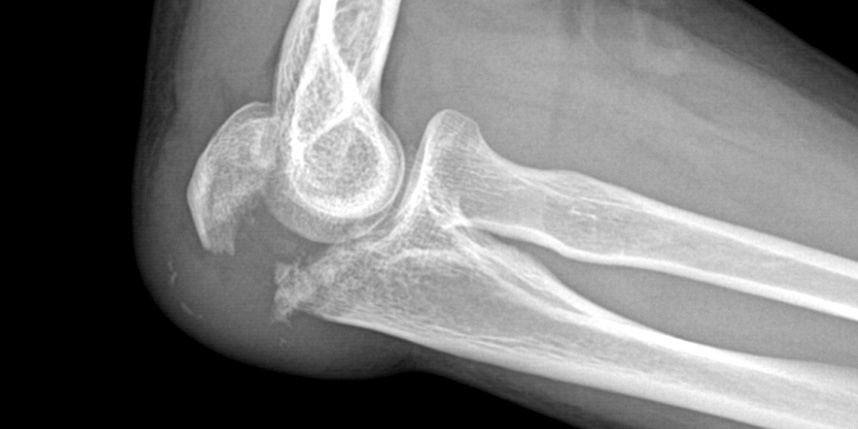

골절은 정확하게 골절편을 잘 맞추고 고정하는 것이 중요합니다. 특히 관절면을 잘 맞추는 것이 중요합니다.

상완골 골절